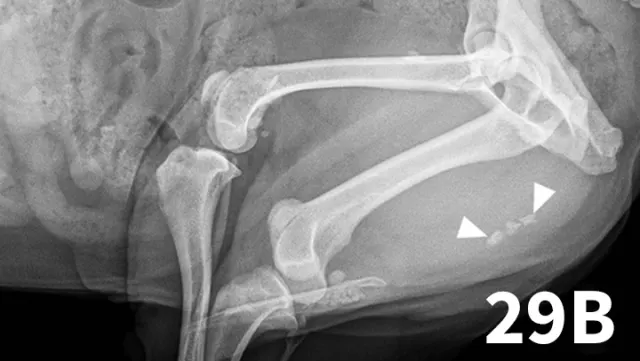

Survey abdominal radiographs (Figures 1 and 2) offer important information on kidney number, size, shape, symmetry, and location, as well as the presence of any mineralized opacities (eg, calcified tissue, nephroliths). The utility of abdominal radiographs is decreased in patients with abdominal fluid or lack of abdominal fat (eg, young or emaciated patients) because of lack of contrast. Excretory urography (IV pyelography), although more invasive, can augment survey radiographs and provide information about renal parenchymal architecture (eg, filling defects associated with cysts or infiltrative disease), the renal pelvis, and ureters as well as a qualitative assessment of global and individual renal excretory function (Figure 3).

An enlarged left kidney with an irregular shape (arrows) is noted on the VD view of a dog with renal adenocarcinoma. The left kidney measured 4.5 times the length of L2; normal kidney length in the dog is 2.5 to 3.5 times the length of L2.